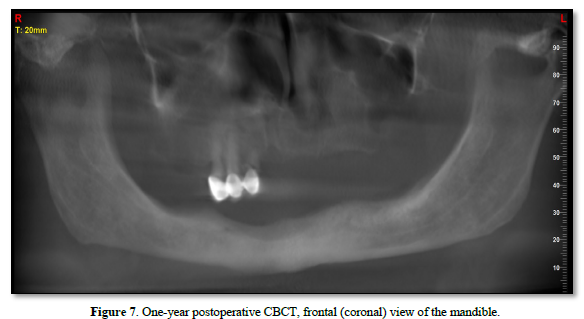

At the one‑year follow‑up, intraoral examination showed complete mucosal healing (Figure 11). CBCT acquired at the same visit—axial, sagittal, and frontal views plus three‑dimensional reconstruction—demonstrated stable bone remodeling of the anterior mandible (Figures 5–8). A one-year postoperative panoramic radiograph also confirmed preserved mandibular continuity, absence of recurrent pathology, and satisfactory bone healing (Figure 12).